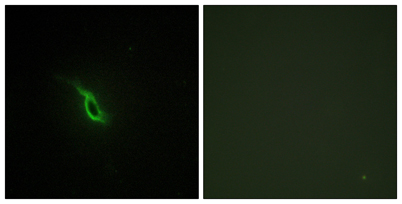

| Dilutions: | Western Blot: 1/500 - 1/2000. Immunohistochemistry: 1/100 - 1/300. Immunofluorescence: 1/200 - 1/1000. ELISA: 1/20000. Not yet tested in other applications. |